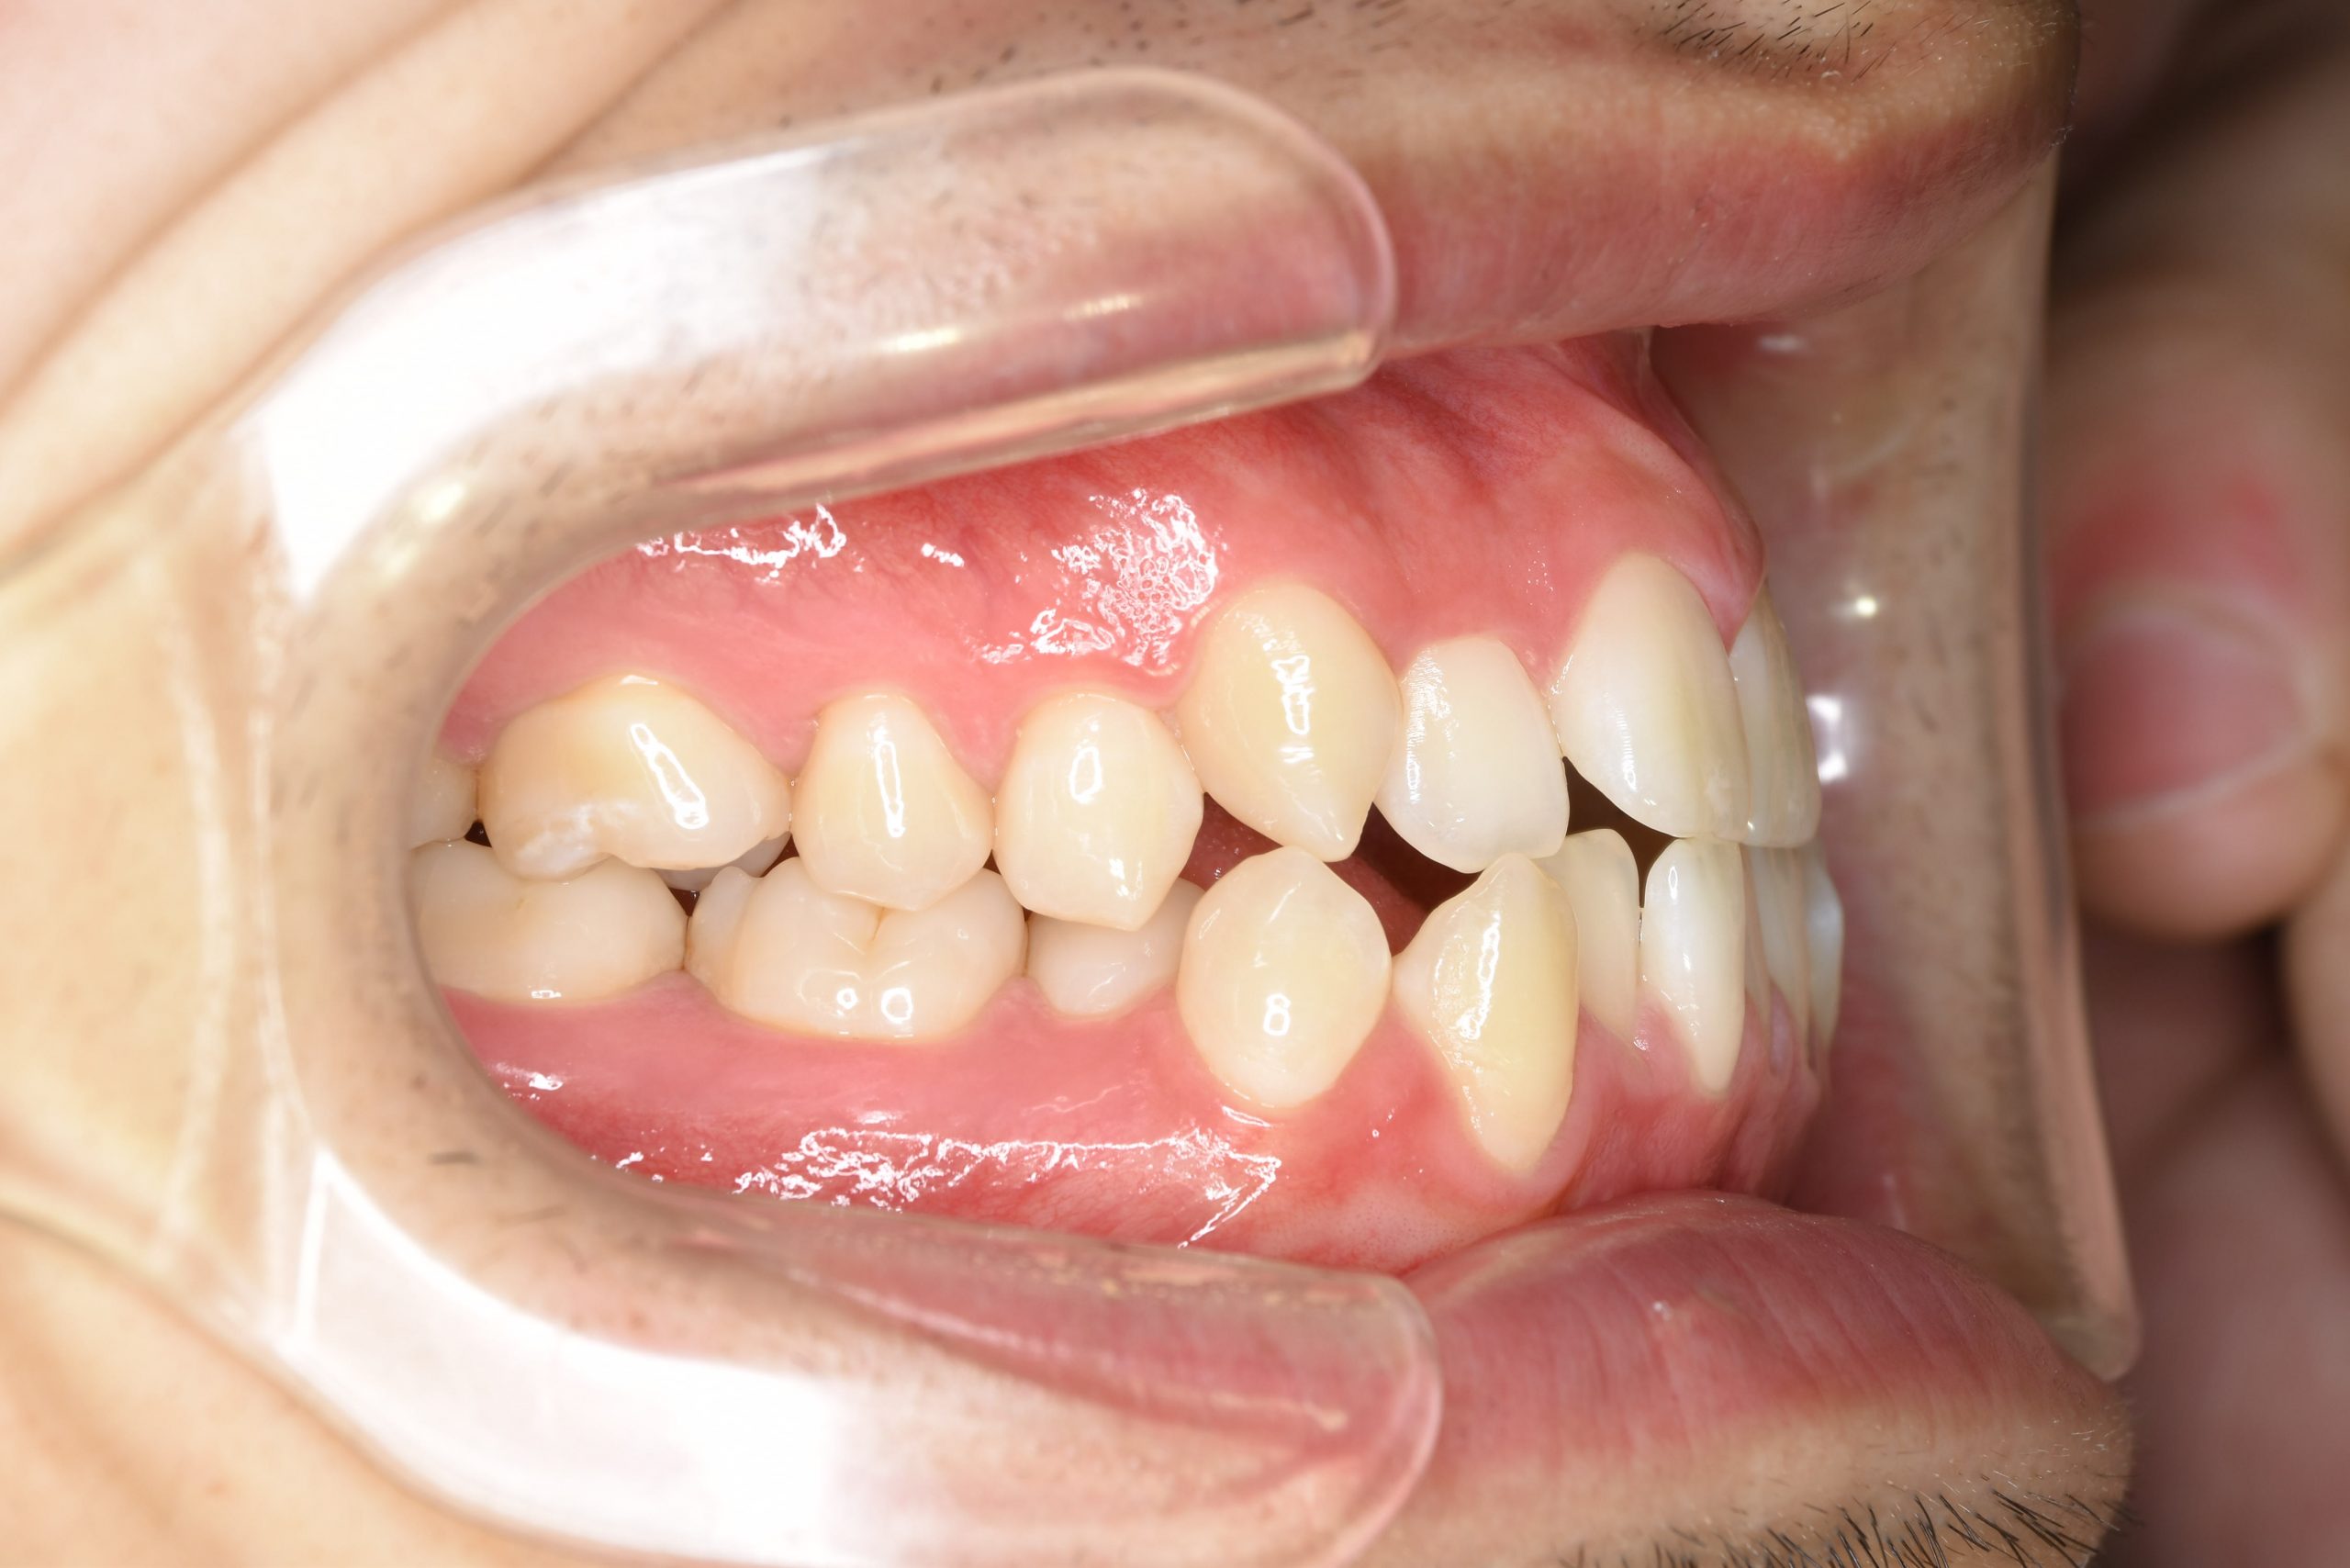

アフター

ワイヤー矯正治療|症例_495

主訴 受け口|かみ合わせ|面長

施術内容 MSEと下顎リンガルアーチを用いて上下顎骨を拡大した。

その後マルチブラケット装置とミニインプラントを用いて

非抜歯で歯牙を配列し、良好な咬合を獲得した。

下口唇の突出感と鼻閉症状は改善した。

治癒期間 2年1か月間